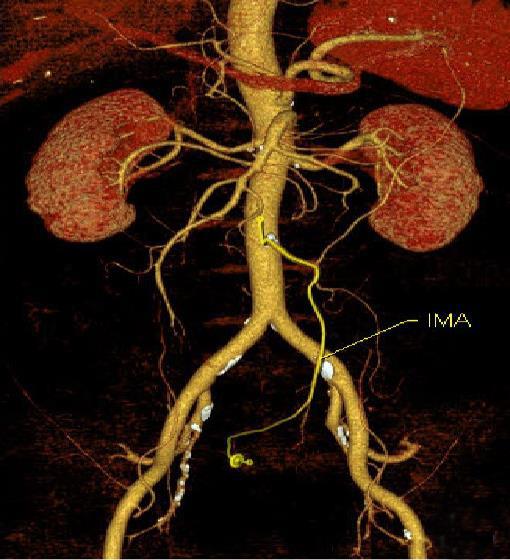

摘要:目的 分析计算机体层摄影血管造影(CTA)在腹腔镜结肠癌根治术前评估中的应用效果。方法 回顾性分析2021年1月-2024年2月于该院接受腹腔镜结肠癌根治术的120例患者的临床资料。其中,60例行常规腹部CT和CTA,60例行磁共振成像(MRI)。以术后病理为金标准,判断CTA对临床T分期与术后病理的一致性,以及评估肿瘤是否侵犯肠系膜血管和周围组织的准确度。结果 术前CTA诊断T分期的准确率为95.00%(57/60),一致性好(Kappa = 0.925,P < 0.05);术前MRI诊断结肠癌T分期的准确率为98.33%(59/60),两者比较,差异无统计学意义(χ2 = 0.26,P > 0.05)。CTA预判肿瘤是否累及肠系膜上动脉、肠系膜上静脉、肠系膜下动脉、肠系膜下静脉、腹主动脉、肾动脉、肾静脉和脾动脉等血管,与术后病理的一致性好。特别是在预测肠系膜血管受累方面,CTA的敏感度为94.44%,特异度为95.83%,准确度高达95.00%。结论 对于行腹腔镜结肠癌根治术的患者,术前CTA不仅能清晰地显示结肠癌T分期,还能揭示肠系膜血管的走行和变异,以及肿瘤与周围组织的关系和侵犯程度,从而为手术规划提供强有力的支持,确保了腹腔镜手术的安全性,减少了不必要的手术风险。